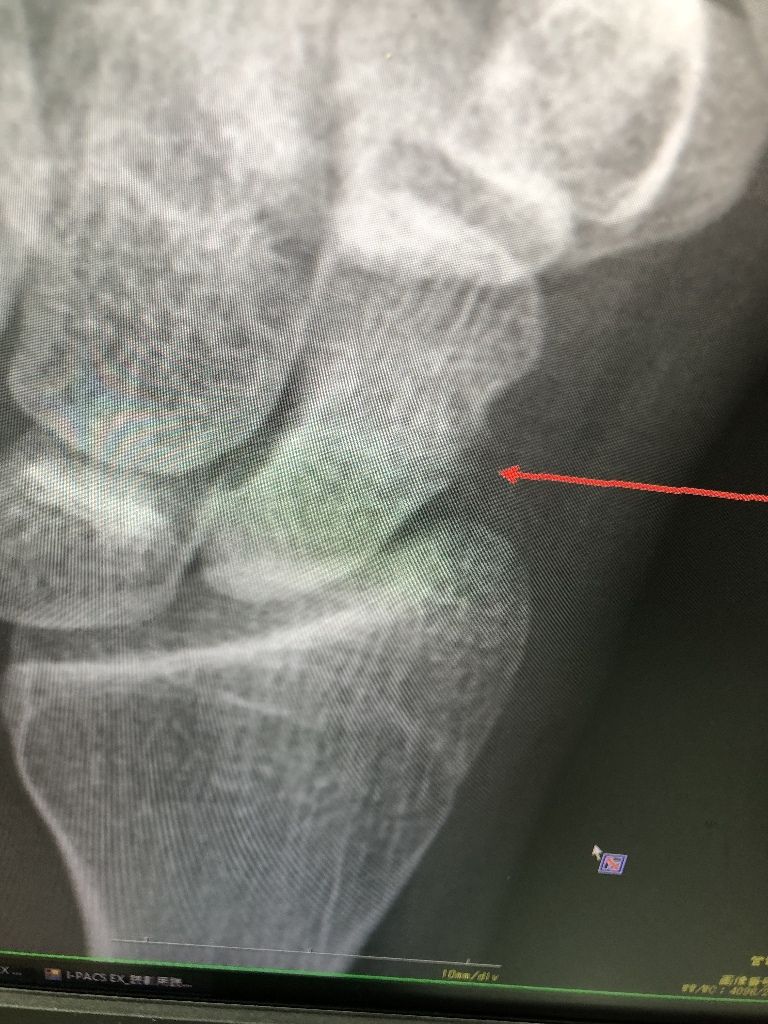

昔はつかなかった骨折も、最近は治療器が良くなり骨癒合できています、

手の骨折です

イメージ 1

骨癒合

イメージ 2